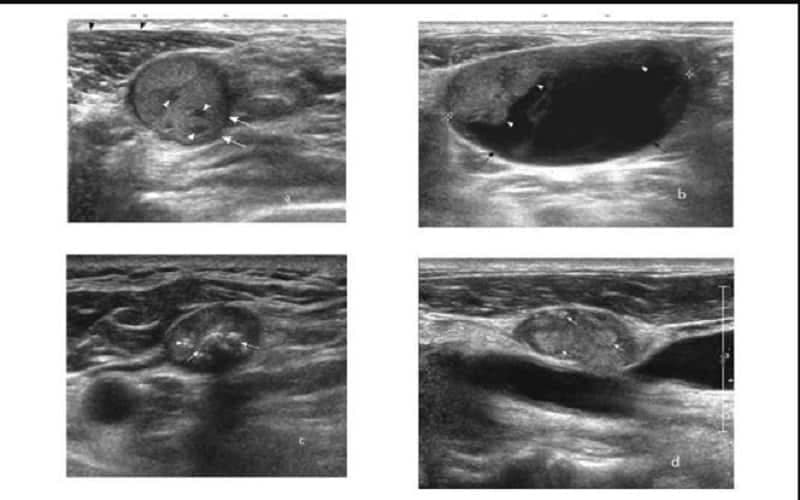

Đặc điểm hạch lành tính trên siêu âm thường dựa trên các yếu tố về kích thước, hình dạng, cấu trúc xoang hạch và sự phân bố mạch máu:

- Về kích thước, hạch lành tính đa số có đường kính trục ngắn ≤ 10mm. Dù một số hạch viêm có thể lớn hơn mức này, nhưng nếu các đặc điểm khác vẫn điển hình thì hướng nhiều đến tính chất lành tính.

- Về hình dạng, hình ảnh siêu âm hạch lành tính có dạng bầu dục hoặc hình elip, với tỷ lệ chiều dài/chiều rộng > 2. Đường bờ rõ ràng, vỏ hạch mỏng và phân bố đều, không có dấu hiệu dày lên bất thường.

- Về cấu trúc bên trong, rốn hạch được bảo tồn và biểu hiện là một vùng tăng âm nằm ở trung tâm hoặc hơi lệch tâm. Cấu trúc xoang hạch còn rõ, không bị phá vỡ. Không thấy các dấu hiệu như hoại tử, vi vôi hóa hay thâm nhiễm bất thường.

- Trên siêu âm Doppler, mạch máu đi vào từ rốn hạch và phân bố theo trục trung tâm. Không ghi nhận hiện tượng tăng sinh mạch ngoại vi hay rối loạn cấu trúc mạch.

- Hạch lao: Là hạch lành tính do vi khuẩn lao gây ra (tuberculous lymphadenitis). Tuy nhiên, trên siêu âm, hạch lao lại mang nhiều đặc điểm giống hạch ác tính nên dễ gây nhầm lẫn. Hình ảnh thường gặp là hạch tròn, hồi âm kém, có vùng hoại tử hóa nang bên trong làm đẩy lệch hoặc phá hủy rốn hạch. Vỏ bao dày, đôi khi bị phá hủy, kèm thâm nhiễm mỡ xung quanh và các hạch có thể tụ lại thành đám.

- Hạch trong lymphoma: Thường tròn, hồi âm rất kém (gần giống nang nhưng không có tăng âm sau). Mất rốn hạch, cấu trúc bên trong dạng lưới, hiếm khi hoại tử nếu chưa điều trị. Đặc điểm thường gặp là xuất hiện nhiều hạch ở nhiều vị trí khác nhau và đối xứng hai bên, vì vậy cần khảo sát thêm vùng nách, bẹn, khoang sau phúc mạc. Lưu ý, bệnh Castleman thường biểu hiện bằng hạch đơn độc.

- Hạch di căn: Có hình tròn, hồi âm kém, mất rốn hạch. Vỏ hạch dày không đều do tế bào ung thư thâm nhiễm. Hoại tử bên trong khá phổ biến, đặc biệt trong carcinoma tế bào sừng. Hạch có thể xuất hiện thành đám, bờ không đều, giới hạn không rõ, gợi ý tình trạng xâm lấn ra ngoài bao hạch và thường liên quan đến tiên lượng xấu.